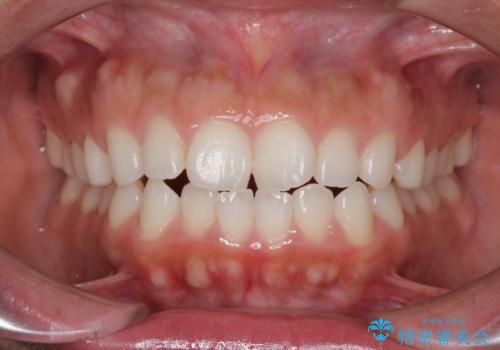

前歯の出っ歯と口の閉じにくさを抜歯矯正で改善 目立たないワイヤー矯正

出っ歯を改善した後に真っ白な歯に 矯正歯科治療と審美歯科治療